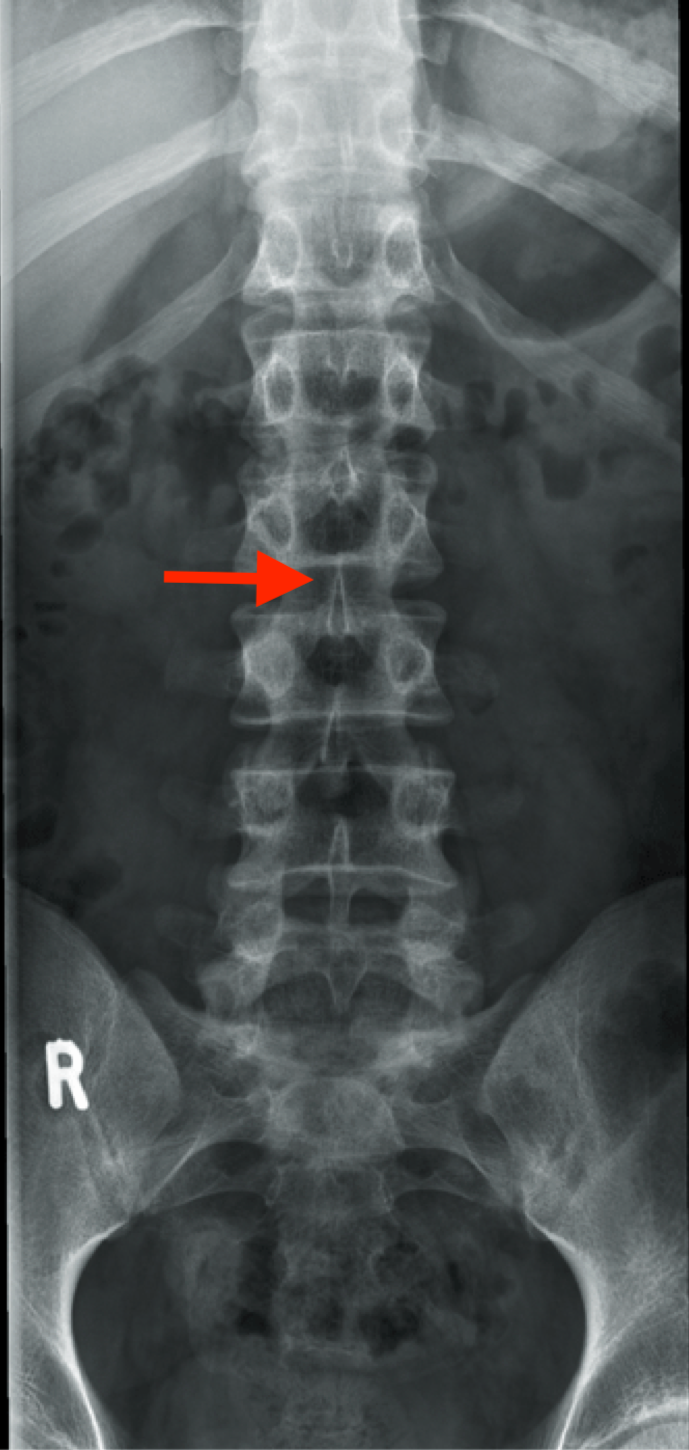

body of T11 contains

one entire articular facet, no articular facet on the TVP

describe TVP of T11

short, no articular facet for rib